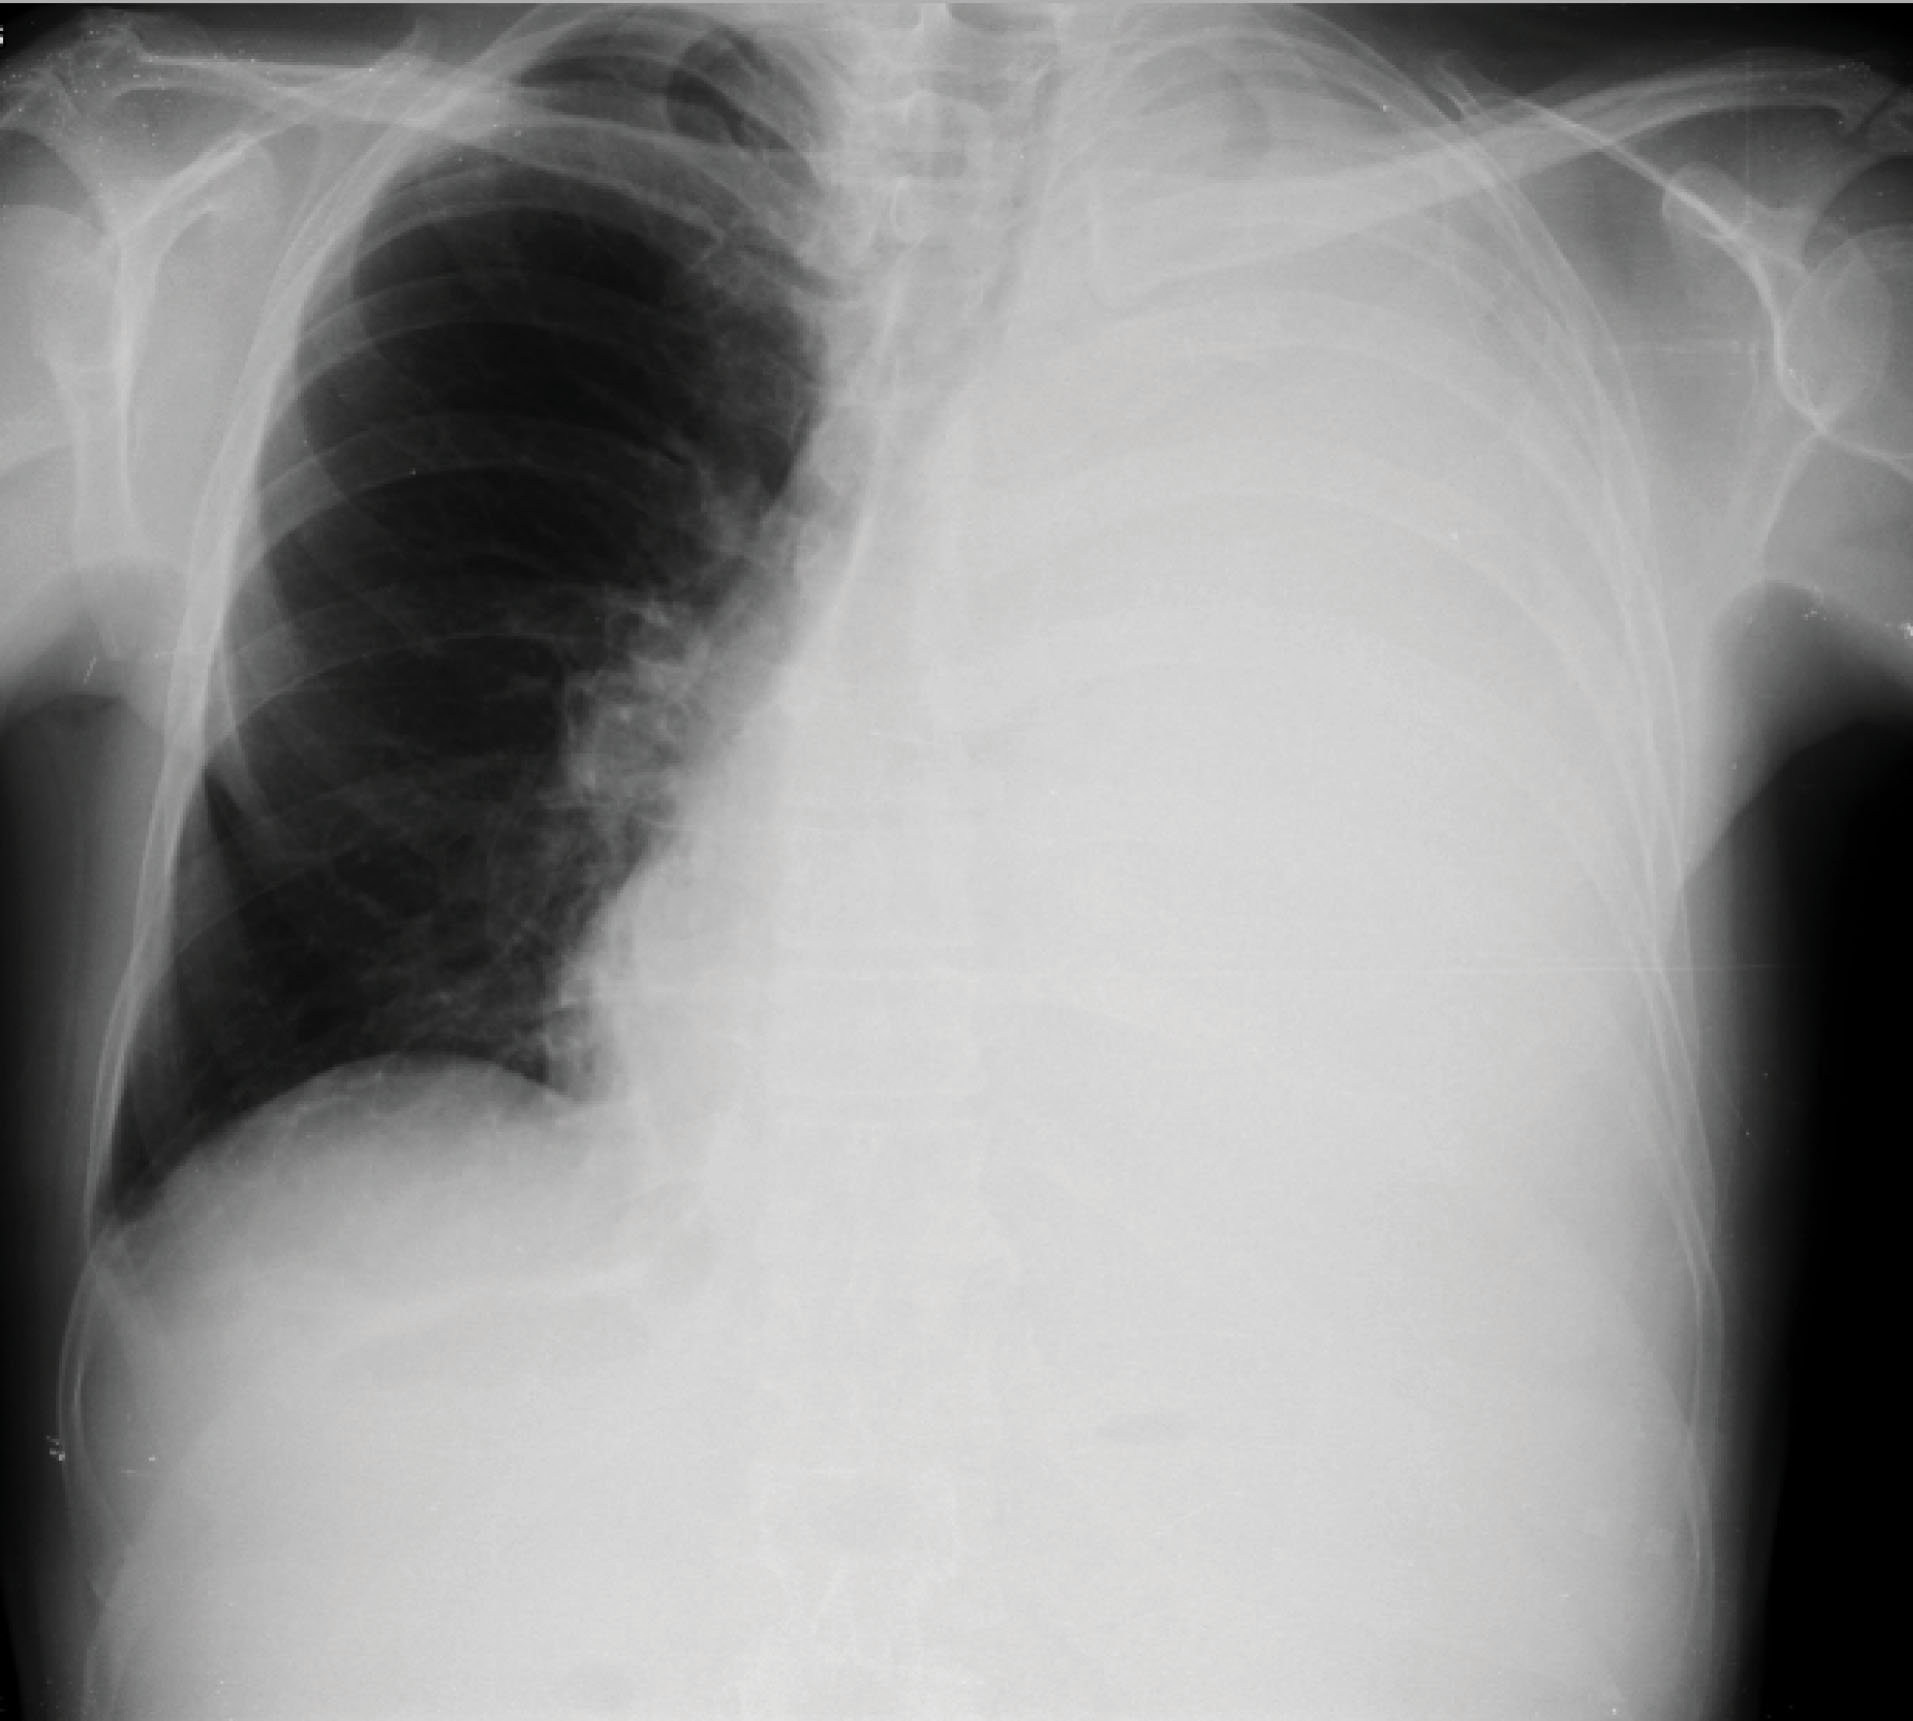

In a second visit to the ER the patient had normal vital signs but a marked decrease in breath sounds throughout the left hemithorax. A chest X-ray was performed, which showed homogeneous opacity in the entire left lung and contralateral deviation of the trachea, compatible with large unilateral pleural effusion (). Diagnostic and evacuating thoracentesis had been performed (drained a dark reddish liquid). The liquid analysis was compatible with an exudate, with a high number of erythrocytes (130 300/Ul); empyema or parapneumonic effusion was excluded. Bacteriological and mycobacteriological cultural examinations (both negative later) and anatomopathological examination (without malignant cells later) were left ongoing. He was discharged for an early pulmonology follow-up visit.

jcvtr-14-67-g001

Figure 1. Chest X-ray before the first thoracentesis